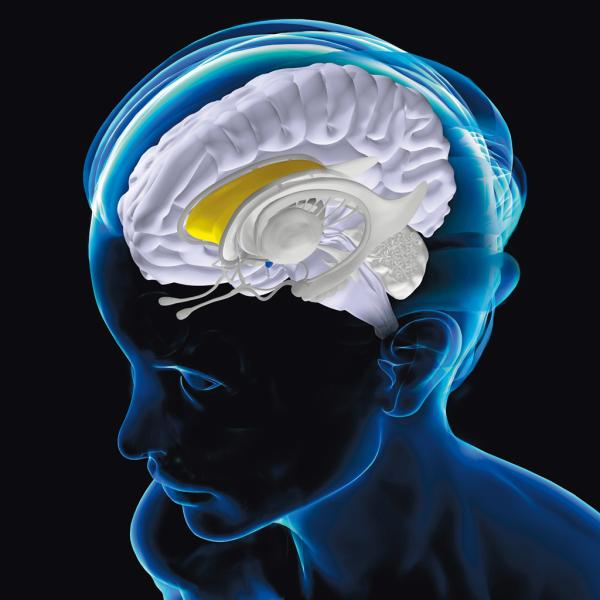

Ludzka pamięć to nie jest jeden wielki magazyn wspomnień, ale sieć skomplikowanych systemów zmuszająca do wytężonej pracy niemal cały mózg.